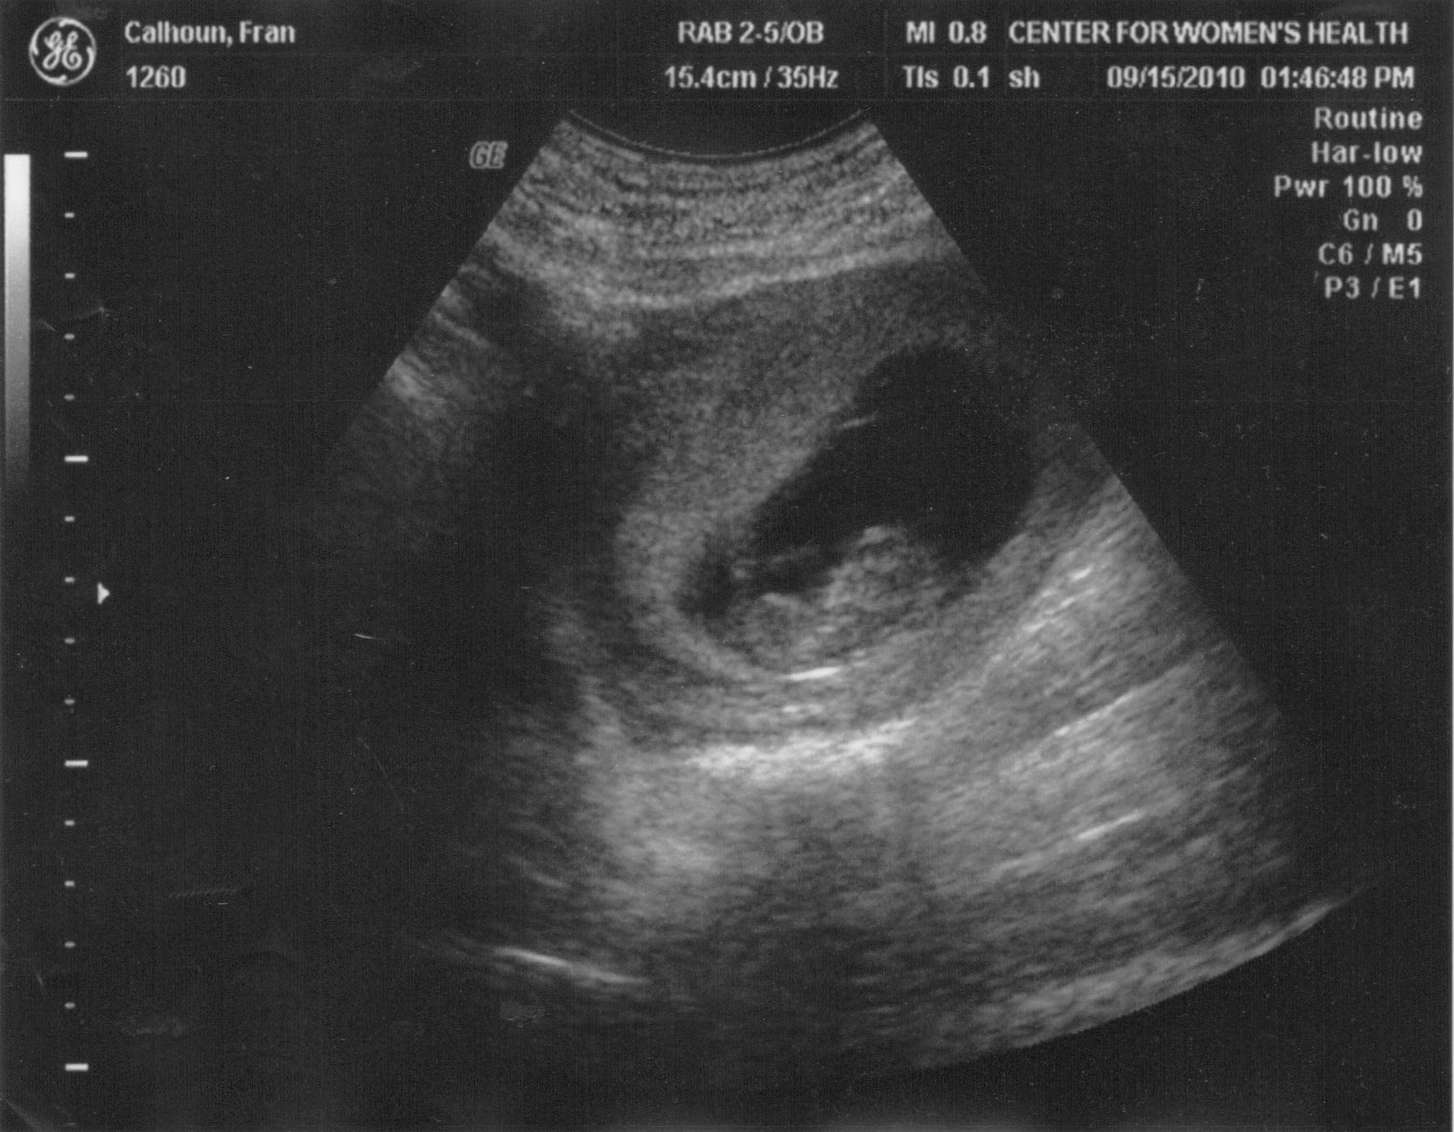

Фото Второй Беременности

Фото Второй Беременности 117 фотографий